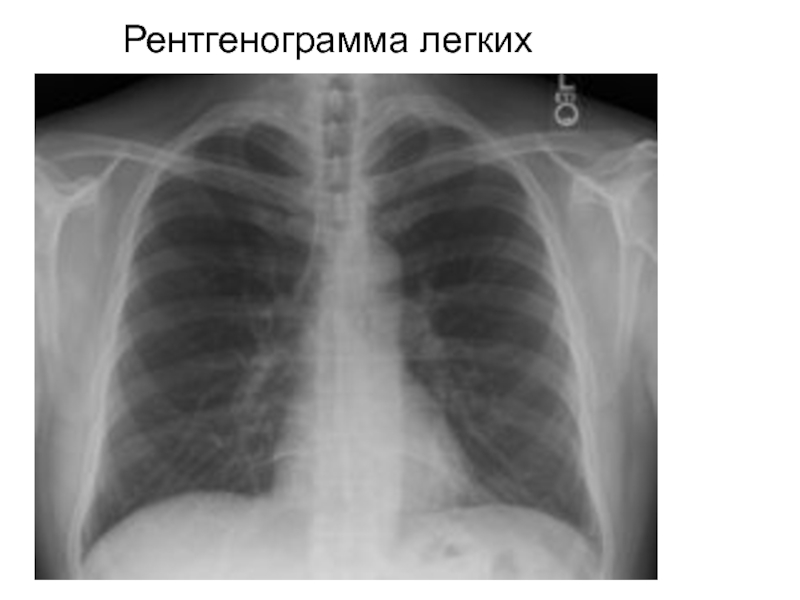

Слайд 38Структуры, различимые на рентгенограмме легких

Легочные поля

Тень средостения

Костные концы ребер

Межреберные промежутки

Ключицы

Корни

легких

Синусы плевры

Структуры, различимые на рентгенограмме легкихЛегочные поляТень средостенияКостные концы реберМежреберные промежуткиКлючицыКорни легкихСинусы плевры

Слайд 39Рентгенограмма легких

Рентгенограмма легких